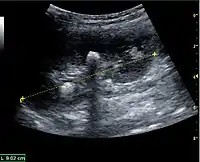

Figure 16. Hydronephrosis with dilated anechoic pelvis and calyces, along with cortical atrophy. The width of a calyx is measured on the US image in the longitudinal scan plane, and illustrated by ‘+’ and a dashed line.[1]

Figure 17. Same patient as in Figure 16 with measurement of the pelvis dilation in the transverse scan plane illustrated on the US image with ‘+’ and a dashed line.[1]